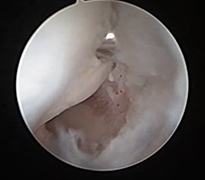

El bileği artroskopisi, el bileği ekleminin küçük kesilerden girilerek kamera ve özel cerrahi aletler yardımıyla değerlendirilmesi ve tedavi edilmesini sağlayan modern bir yöntemdir. Bu teknik sayesinde eklem içi yapılar detaylı şekilde görüntülenebilir. Özellikle bağ yaralanmaları, kıkırdak hasarları, TFCC (üçgen fibrokartilaj kompleks) lezyonları ve bazı kırık sonrası problemlerinin tanı ve tedavisinde kullanılır. Hastalar genellikle el bileğinde ağrı, hareket kısıtlılığı veya tıklama hissi ile başvurur.

Artroskopik yöntem, açık cerrahiye göre daha küçük kesilerle yapıldığı için doku hasarı daha azdır ve iyileşme süreci genellikle daha hızlıdır. İşlem sırasında hem tanı konulabilir hem de gerekli onarımlar aynı seansta gerçekleştirilebilir. Ameliyat sonrası kısa süreli istirahat ve ardından kontrollü egzersiz programı önerilir. Uygun hastalarda el bileği artroskopisi, ağrının azaltılması ve fonksiyonun geri kazanılması açısından etkili ve güvenilir bir tedavi seçeneğidir.